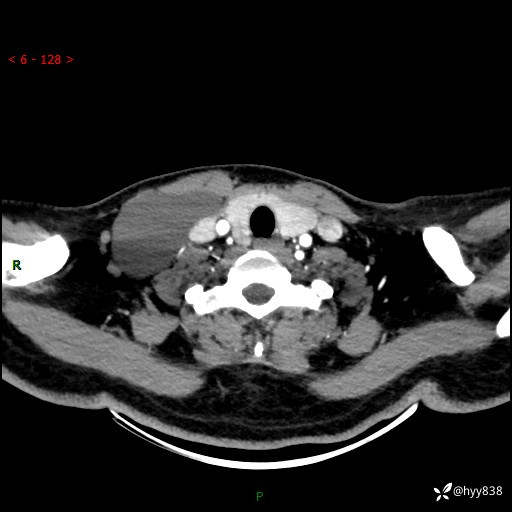

增强动脉期+静脉期